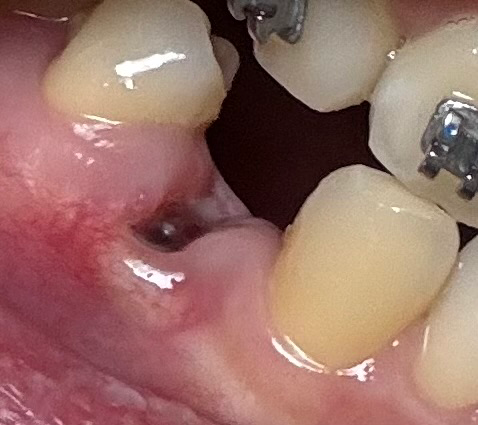

발치를 하고 나서 시간이 지나면서 나타나는 정상적인 회복패턴 중 하나입니다. 보통 섬유화가 진행되면서 주변이 하얗게 변하고 붉게 변하다가 자연스럽게 잇몸 조직과 비슷하게 됩니다. 특별히 치료를 해야 하는 것이 아니며 시간이 지나면 모두 정상적인 잇몸이 될 것으로 보입니다.

사진상으로 크게 문제가 되는건 없어 보입니다. 잘아물고 잇는거 같으니 너무 걱정하지 않으셔도 될것같습니다.

사진으로만 봤을 경우에는 혈병이 잘 형성되어 있고 염증이 없는 것으로 보입니다. 발치한 부위가 잘 아물기 위해서는 해당 부위가 자극이 되지 않는 것이 좋으니 조심히 관리를 해주는 것이 좋습니다.

염증이 생긴 것은 아니며 치료되는 과정입니다. 사진상으로 문제는 안보이니 잘 관리하면 됩니다.

특별히 치유 과정에 있어서 문제는 없어 보입니다. 다만, 아직까지 발치 부위 잇몸이 온전히 아물지 않았습니다. 해당 부위로 음식물이 잘 끼어 있을 수 있기 때문에 될 수 있으면 양치질을 해당 부위도 살살 해주면서 음식물을 잘 빼주어야 합니다.